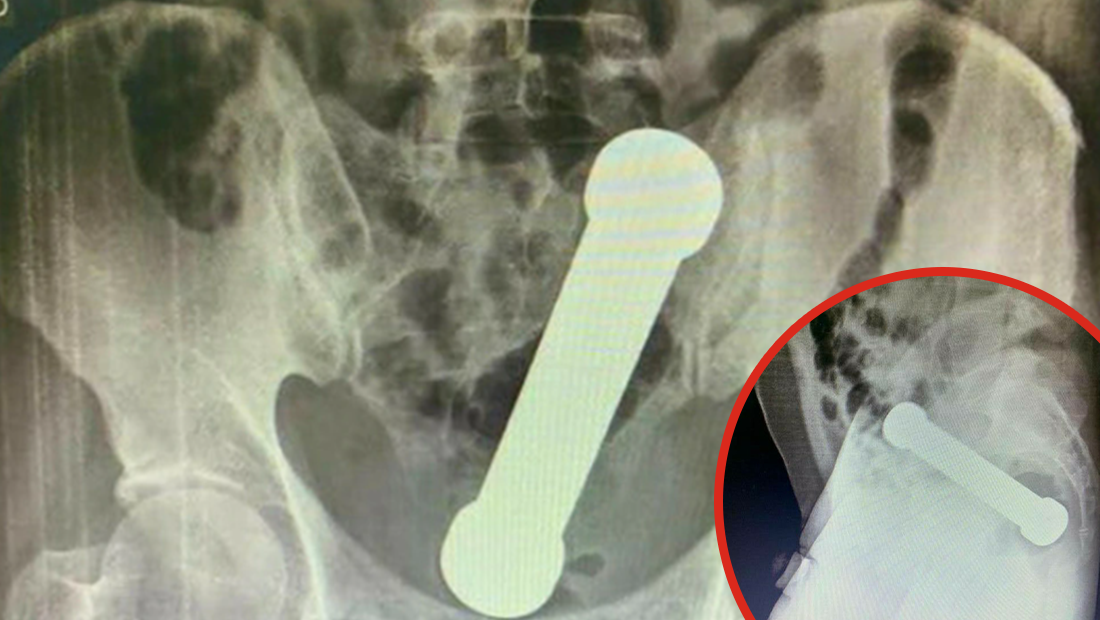

After X-rays were conducted, doctors found the 20cm -long-dumbbell wedged in where the colon meets the rectum. Ya can't miss it.